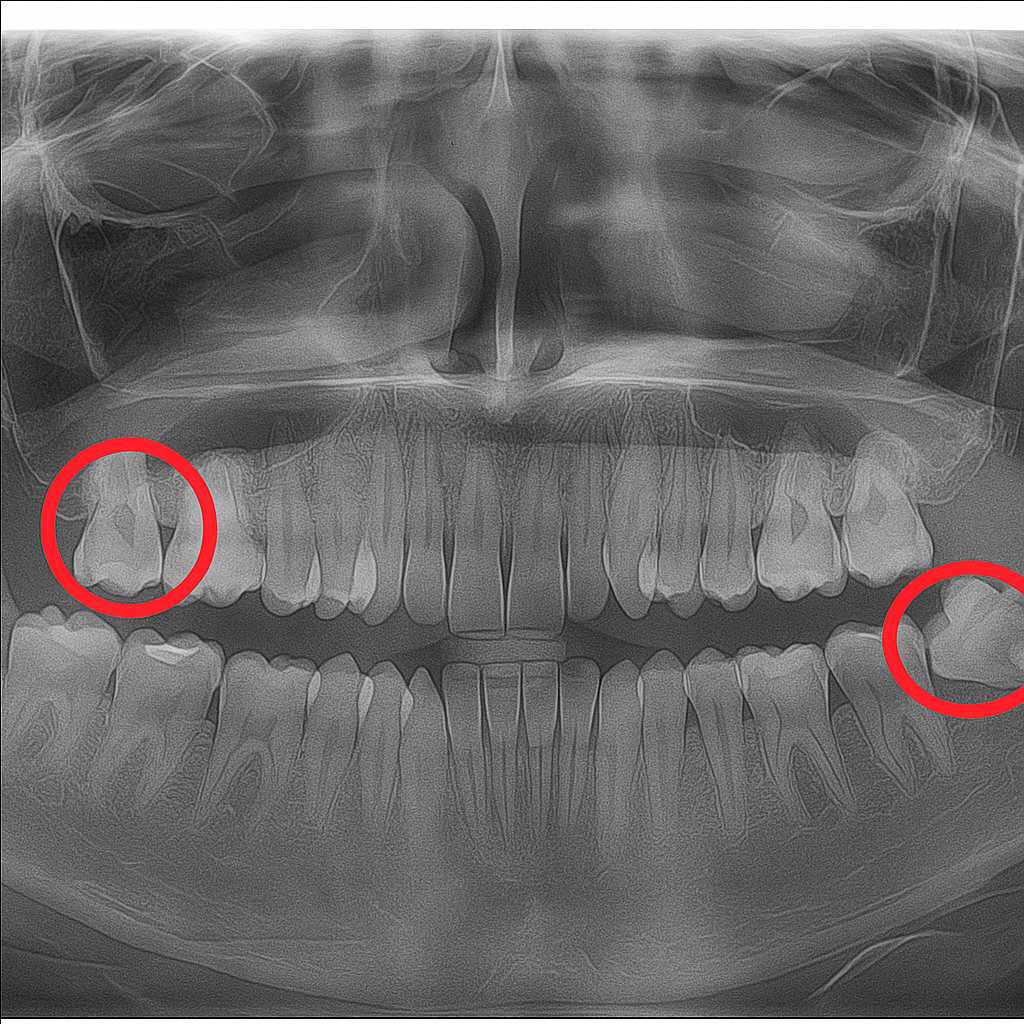

Impacted Wisdom Teeth

Impacted wisdom teeth are third molars that don’t fully erupt due to lack of space or misalignment, often causing pain, swelling, or infection. At Tafodent, we specialize in the safe and gentle removal of impacted wisdom teeth to prevent complications and protect oral health.

- Comprehensive evaluation with digital X-rays

- Surgical extraction of partially or fully impacted wisdom teeth

- Local anesthesia or sedation options for a pain-free experience

- Post-operative care instructions and follow-up support

- Prevention of crowding, infection, and damage to nearby teeth